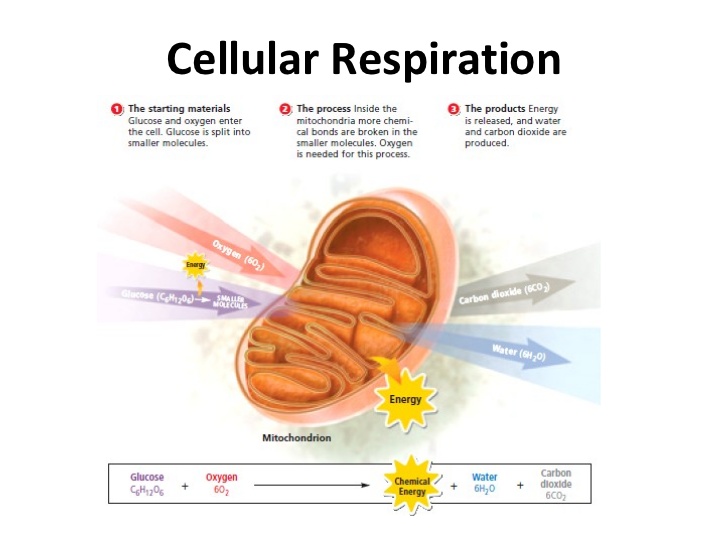

2. Cellular Respiration:

This is the process by which oxygen breathed in from the atmosphere is used in the breaking down of food substances in our body cells to release needed energy with CO2 and H2O as the waste products.

TYPES OF RESPIRATION

1. External Respiration:

This is breathing which involves exchange of gases and it takes place in the lungs. This simply involves the breathing of air or oxygen into the lungs. This is also called inspiration or inhalation and the breathing out of air (carbon dioxide and water vapour) into the atmosphere and environment is otherwise called expiration or exhalation.

2. Internal Respiration:

This involves the breaking down of food substances and release of energy. It takes place within the cells of the body.

2. Cellular Respiration:

This is the process by which oxygen breathed in from the atmosphere is used in the breaking down of food substances in our body cells to release needed energy with CO2 and H2O as the waste products.

TYPES OF RESPIRATION

1. External Respiration:

This is breathing which involves exchange of gases and it takes place in the lungs. This simply involves the breathing of air or oxygen into the lungs. This is also called inspiration or inhalation and the breathing out of air (carbon dioxide and water vapour) into the atmosphere and environment is otherwise called expiration or exhalation.

2. Internal Respiration:

This involves the breaking down of food substances and release of energy. It takes place within the cells of the body.